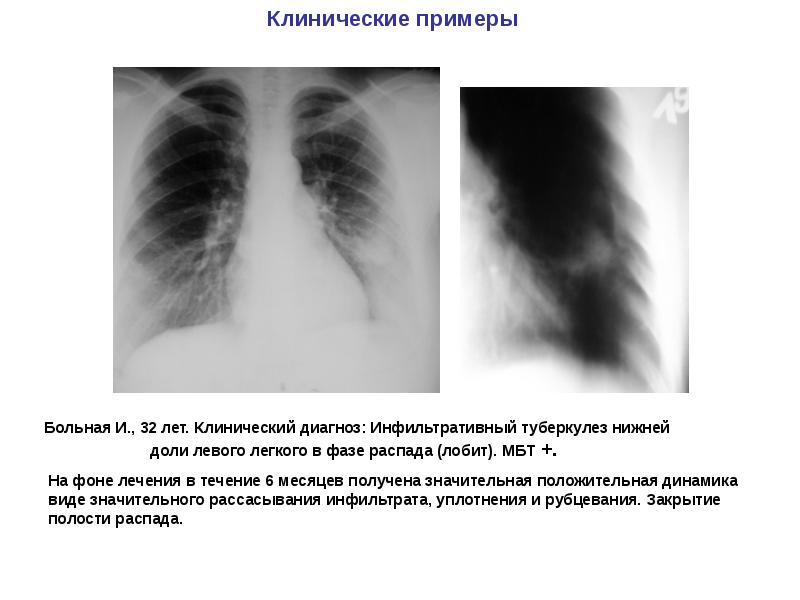

Симптомы и лечение инфильтративного туберкулеза легких

Раздел: Снимки-откровения